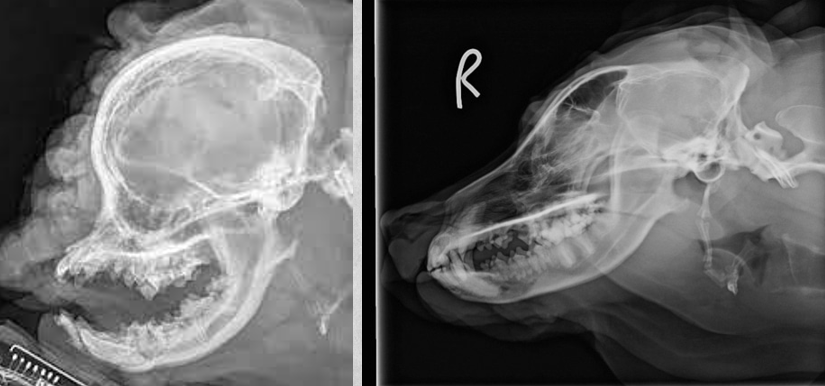

17

Q

identify pathology

A

Hydrocephalus

Note the open fontanelle as well.

7 mo Staffordshire terrier mix